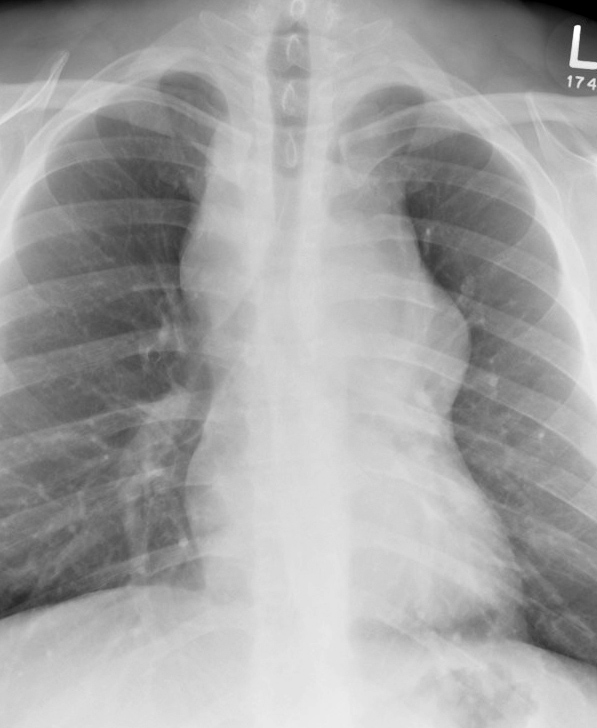

Gallery Mediastinum Lymphoma 5a

5a